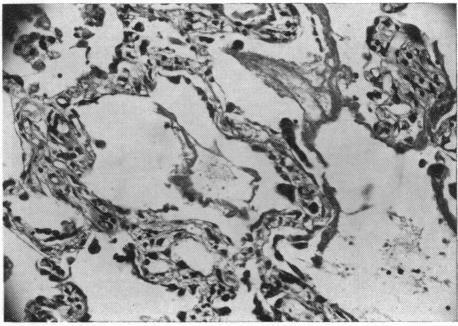

Interstitial pneumonias present a pulmonary inflammatory reaction pattern that is common to a wide variety of noxious agents and disease processes. These include viruses, Rickettsiae, hypersensitivity reactions, the "collagen disease," x-irradiation, uremia, certain chemicals, early histoplasmosis, toxoplasmosis and possibly unknown substances and diseases. Interstitial pneumonia is characterized histologically by interalveolar exudate, hyaline membranes, epithelialization of alveolar walls and lack of polymorphonuclear response. Histologic features that aid in differentiating among cases of varying etiology are few. It is postulated that the basic pathogenic mechanism of the interstitial inflammatory reaction is primary damage to pulmonary capillary endothelium that brings about increased capillary permeability.

间质性肺炎呈现出一种肺部炎症反应模式,这种模式在多种有害因子和疾病过程中很常见。这些包括病毒、立克次氏体、超敏反应、“胶原病”、X线照射、尿毒症、某些化学物质、早期组织胞浆菌病、弓形虫病以及可能的未知物质和疾病。间质性肺炎在组织学上的特征是肺泡内渗出、透明膜形成、肺泡壁上皮化以及缺乏多形核反应。有助于区分不同病因病例的组织学特征很少。据推测,间质性炎症反应的基本致病机制是肺毛细血管内皮的原发性损伤,这导致毛细血管通透性增加。